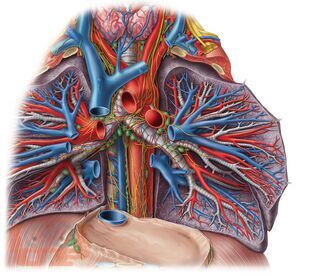

Переработанное и дополненное 3-томное издание «Sobotta. Атлас анатомии человека» является современным учебным пособием. Новое издание атласа отличается от предыдущих клинической направленностью преподавания анатомии: приведено большое количество клинических наблюдений, подтверждающих значение глубоких фундаментальных знаний анатомии при диагностике и лечении различных патологий. Это в полной мере соответствует современным требованиям, предъявляемым к медицинскому образованию, и адаптировано к новым образовательным стандартам. Атлас структурирован по региональному принципу, что соответствует темам учебных сертификационных циклов. Первый том включает разделы общей анатомии, а также подробно иллюстрирует строение костей, их соединений и мышц туловища и конечностей. Упрощенные схемы вводного характера и общие обзоры помогают понять более сложные рисунки и связи. Второй том посвящен анатомии внутренних органов грудной, брюшной полостей и органов таза. В третьем томе представлена анатомия органов головы, шеи, большой раздел посвящен нейроанатомии. Новое издание содержит высококачественные иллюстрации, дополненные подробными подрисуночными подписями. Оригинальные рисунки сопровождаются современными изображениями, полученными с помощью компьютерной и магнитно-резонансной томографии, ультразвуковых и эндоскопических методов исследования, а также интраоперационными цветными фотографиями внутренних органов и т.д. К атласу прилагаются таблицы, содержащие краткую систематизированную информацию об анатомии и о функциях мышц, суставов и об их иннервации. Использование в атласе трехъязычной терминологии повышает интерес к нему со стороны иностранных студентов, обучающихся медицине в России.